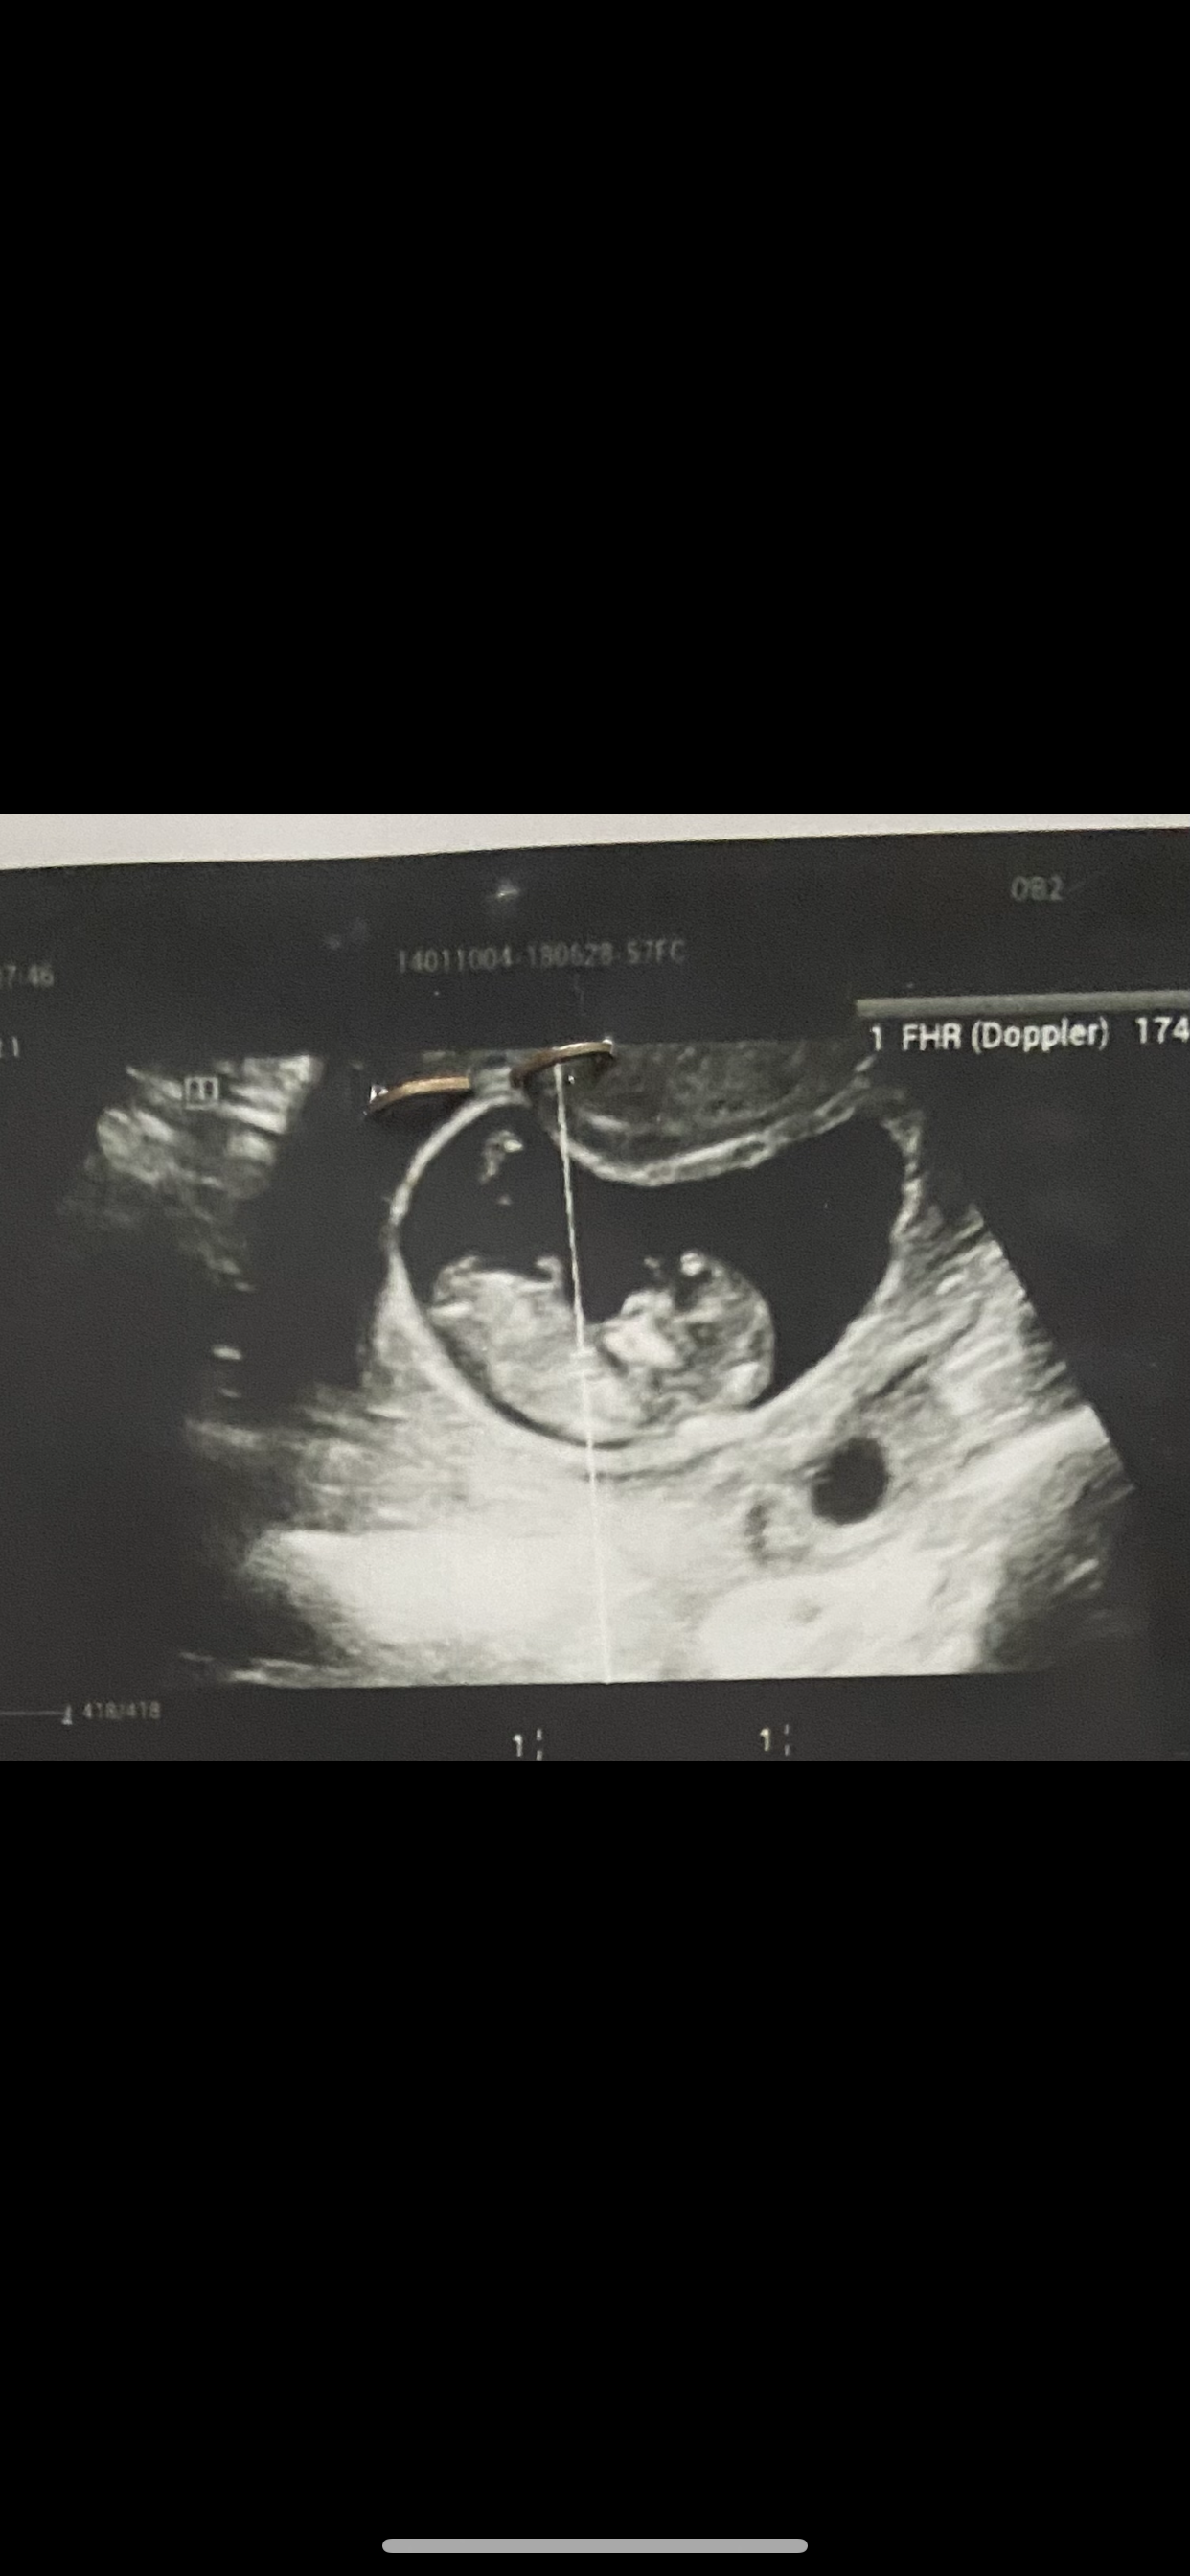

ftmh75 مدیر استارتر عضویت: 1401/07/25 تعداد پست: 299 عنوان متخصصین جنسیت از روی ان تی😙 656 بازدید | 95 پست میشه هر کی میدونه از روی عکس بگه؟🥺حدسی و حس ششمی نگید مرسی😘 1401/11/08 | 14:01 1 نفر لایک کرده اند ... گزارش تاپیک نامناسب

ftmh75 مدیر استارتر عضویت: 1401/07/25 تعداد پست: 299 پسره سونو ان تی گف پسر انومالی ۱۵ هفته گف دختر بنظرتون میشه اشتباه باشه نظرشون؟

اردییبهشتی عضویت: 1400/09/10 تعداد پست: 2849 سونو ان تی گف پسر انومالی ۱۵ هفته گف دختر بنظرتون میشه اشتباه باشه نظرشون؟ من از جمجمه میفهمم برای خودم که باردار بودم تشخیص دادم درست بود